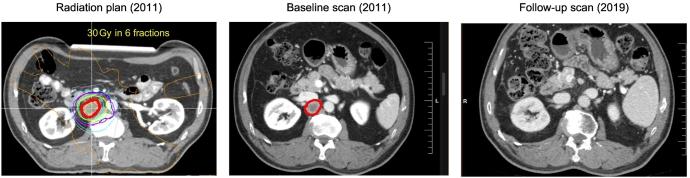

Stereotactic body radiation therapy (SBRT) has an evolving role in the management of hepatocellular carcinoma (HCC), largely due to recent advances in imaging technology. Often utilized in situations where other locoregional therapies are not feasible, SBRT has been demonstrated to be an effective treatment that confers high rates of durable local control. However, there is limited evidence to firmly establish its place in the treatment paradigm for HCC. In this article, we review the current evidence and highlight specific considerations in the multiple settings where SBRT may be used, including for primary HCC treatment and bridging/downstaging, as well as exploring the potential for SBRT in the treatment of extrahepatic oligo-metastatic HCC.

立体定向体部放射治疗(SBRT)在肝细胞癌(HCC)的治疗中作用不断演变,这主要归因于近期成像技术的进展。SBRT常用于其他局部区域治疗不可行的情况,已被证明是一种有效的治疗方法,能带来较高的持久局部控制率。然而,尚无充分证据能确定其在HCC治疗模式中的地位。在本文中,我们回顾了当前证据,并强调了SBRT在多种应用场景中的具体考量因素,包括原发性HCC的治疗以及桥接/降期治疗,同时探讨了SBRT在肝外寡转移HCC治疗中的潜力。